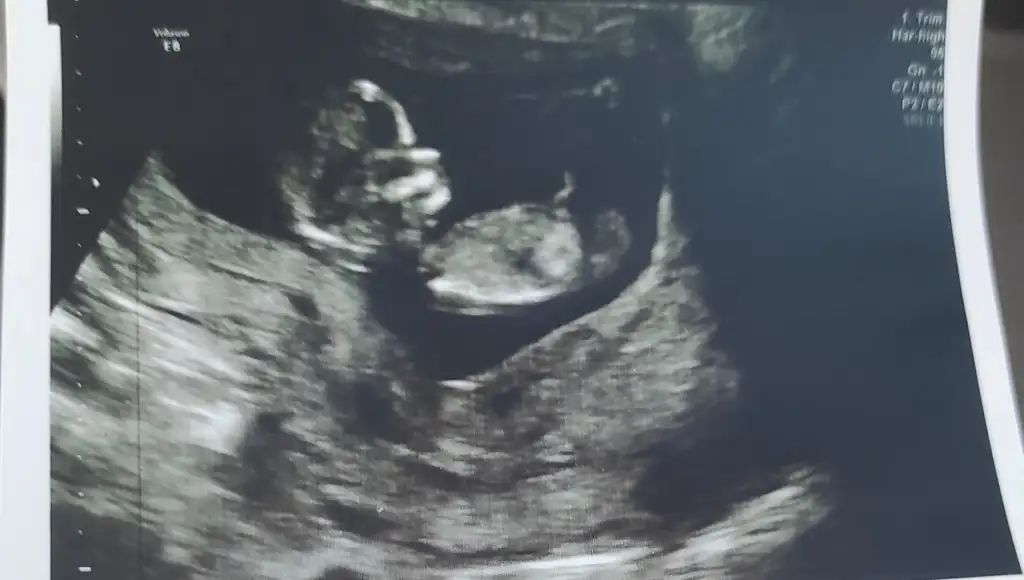

Tahmini olan var mıı 13+5 haftalk

Eklentiler

• 2A043655-A168-417A-A685-75C2D17BEA7B.webp

2A043655-A168-417A-A685-75C2D17BEA7B.webp

21 KB · Görüntüleme: 145